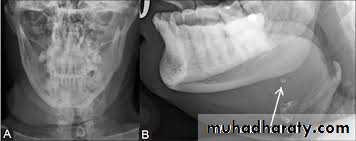

It may occur at any age, common in the middle aged, pain and swelling during eating and xerostomia. On examination the stone may palpated, especially if present at the peripheral aspect of the ductInvestigations:

1. Radiographs: OPG, Posteroanterior, True lateral, oblique lateral of mandible or intraoral occlusal views shows the calcified stone.2. Sialography: reveals dilation of the duct and site of the stone even if it is un calcified (radiolucent).